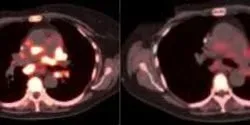

Using human triple-negative breast cancer cells grown in mice, the research team tested a naturally occurring, non-toxic plant compound called luteolin to determine if it could suppress metastasis